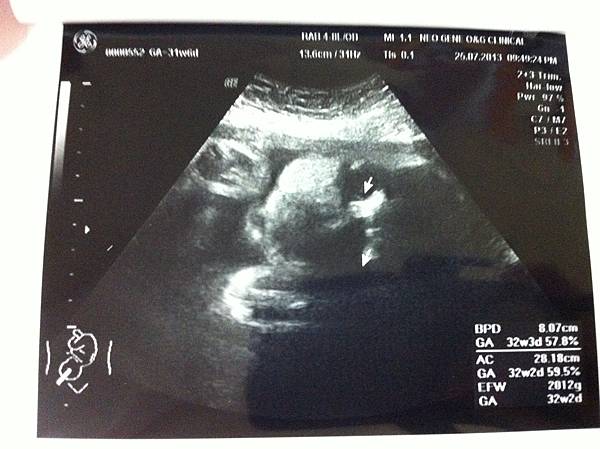

此次檢查週數:31週6天

佑佑體重:2012g